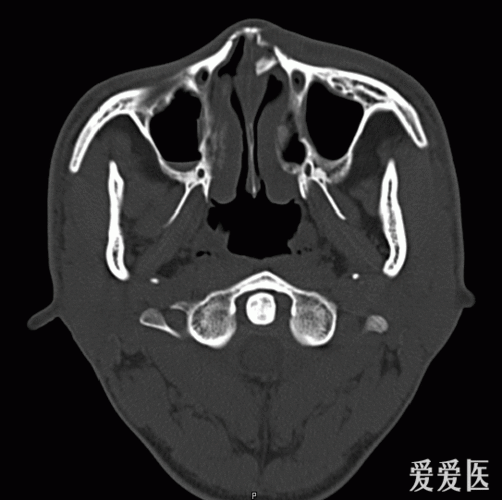

鼻骨骨折